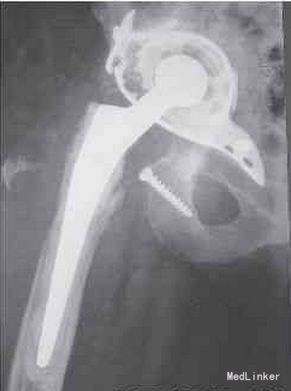

患者为84岁女性,因右髋关节疼痛入院。在过去的数月中,疼痛逐渐加重,活动明显受限。近来其疼痛、关节僵硬度以及右髋周围发热情况加重。检查发现,在右侧髋关节手术瘢痕周围有一直径约8cm的紫褐色皮损区,其内可见6个结节,呈暗黑色(图1)。右侧大腿近端的皮损区肿胀,可见一直径约24cm的红斑区延伸至腹股沟区。 患者白细胞计数正常,为8.3×109/L,中性粒细胞计数升高,为81.6×109/L,C反应蛋白增高至86mg/L。右髋关节X线片显示Burch-Schneider网架断裂并移位,右侧股骨近端有明显的骨溶解(图2)。